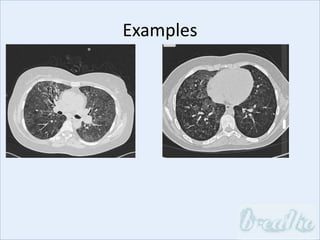

Examples